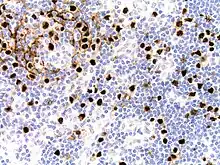

| Micrograph of HHV8-associated Castleman's Disease showing LANA-1 positive lymphoblasts in a regressed germinal center and mantle zone. LANA-1 stain. | |

Staining with latency-associated nuclear antigen (LANA-1), a marker for HHV-8 infection, is typically positive.[11]